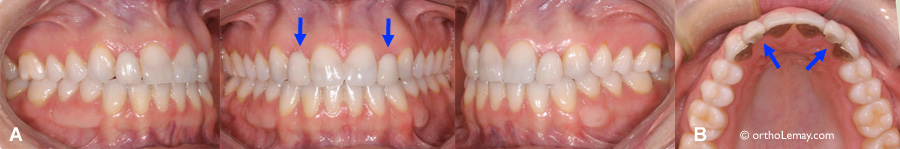

La position trop inclinée des incisives centrales supérieures empêchera la pose d’implants dentaires pour remplacer les incisives latérales manquantes. (A) Avant le traitement : les flèches bleues indiquent les incisives latérales manquantes. (B) Ces incisives latérales sont remplacées par des dents prothétiques collées aux dents adjacentes. (C) Une radiographie panoramique confirme la mauvaise position des incisives centrales. (D) Vue agrandie de la radiographie et implants ajoutés comme simulation. Les pointillés bleus représentent la position idéale que devraient avoir les incisives centrales. (E) Cette patiente a opté pour une technique de broches linguales pour des raisons esthétiques.

Cas CP: Anodontie des incisives latérales et position inadéquate des incisives centrales pour la pose d’implants dentaires.

Femme de 20 ans désirant remplacer ses incisives latérales manquantes à l’aide d’implants dentaires. Ce cas est similaire au précédent; la jeune femme a eu un premier traitement d’orthodontie à l’adolescence, mais la position des racines des incisives centrales supérieures ne permet pas au dentiste de poser des implants convenablement. Afin de maximiser les chances de succès, il a donc recommandé d’avoir recours à l’orthodontie pour mieux aligner les racines des dents antérieures, particulièrement les incisives centrales.

Dans ce type de cas, bien que 2 dents soient principalement visées par ces corrections (les incisives centrales dans le cas ci-dessous et les incisives latérales dans le cas précédent), il est nécessaire de poser des appareils sur au moins les 6 dents antérieures et une dent postérieure pour bien contrôler la mécanique orthodontique et les forces utilisées.

Le plan de traitement vise donc uniquement à changer la position des incisives centrales en inclinant les racines vers le centre.

Lorsque l’orthodontiste croit que les dents sont en bonne position, une vérification radiologique est faite et le patient est dirigé vers le dentiste qui fera la pose des implants pour une vérification finale et approbation des correctifs apportés.